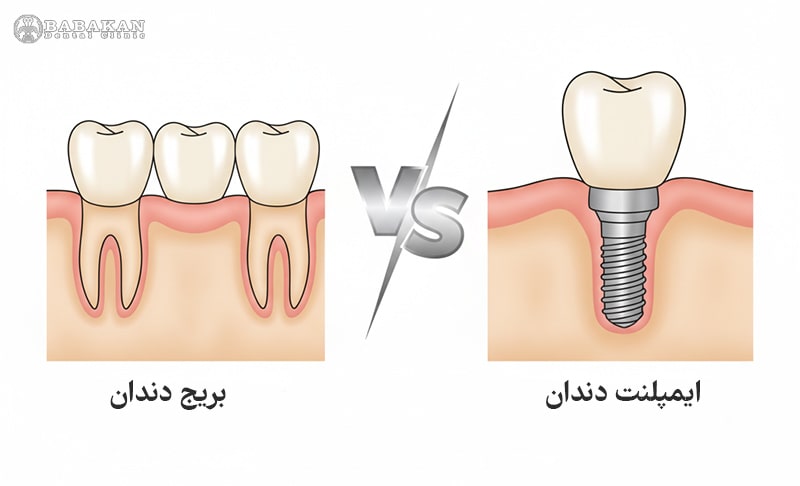

بریج دندان (Dental Bridge) نوعی پروتز ثابت است که با تکیه بر دندانهای مجاور، جای خالی دندان از دسترفته را پر میکند. در این روش، معمولاً دندانهای کناری تراشیده میشوند تا بتوانند نقش پایه بریج را ایفا کنند. در مقابل، ایمپلنت دندان (Dental Implant) پایهای فلزی و پیچشکل است که مستقیماً درون استخوان فک جای میگیرد و بهمرور با استخوان جوش میخورد. سپس یک تاج دندانی روی آن قرار میگیرد که کاملاً شبیه دندان طبیعی عمل میکند و نیازی به آسیب به دندانهای اطراف ندارد.

برای مقایسه پل دندان و ایمپلنت، در ابتدا باید به تعریف هر کدام از این موارد بپردازیم. در روش پل دندان یا بریج، دندان های کناری به عنوان پایه دندان از دست رفته، مورد استفاده قرار می گیرند. در واقع دندانپزشک برای پر کردن جای خالی دندان از دست رفته، از بریج استفاده می کند. بریج نوعی دندان مصنوعی ثابت است که از یک یا چند دندان و دو روکش در دو سمت آنها تشکیل شده است.

این روکش ها با قرارگیری بر روی دندان های اطراف دندان از دست رفته، می توانند ثبات دندان مصنوعی را حفظ کنند. برای ساخت پل دندان، از مواد مختلفی مانند سرامیک، طلا، چینی و … استفاده می شود که نوع سرامیک آن به دلیل شباهت ظاهری زیاد به دندان طبیعی، طرفداران بیشتری دارد. بریج ها انواع مختلفی دارند که شامل سنتی یا ساده، کانتیلور یا معلق، بریج مریلند و همراه با ایمپلنت می شوند. حال ایمپلنت نیز به پل دندانی شباهت زیادی دارد؛ با این تفاوت که در بریج ها پایه دندان، همان ریشه اصلی دندان است.

اما در ایمپلنت، با ایجاد یک ریشه مصنوعی، یک پایه برای روکش دندان تشکیل می دهند. این روزها ایمپلنت، یکی از بهترین راهکارها برای جبران دندان از دست رفته است. این روش، تاثیر به سزایی در ظاهر، تکلم و بهبود جویدن غذا دارد. کاشت ایمپلنت دندان، انواع مختلفی دارد که شامل ایمپلنت های تک دندان، دندان فوری، بر اساس پونتیک، جراحی های لیفت سینوس و جراحی بازسازی استخوان فک می شود. هر کدام از این دو روش، دارای مزایا و معایبی هستند.